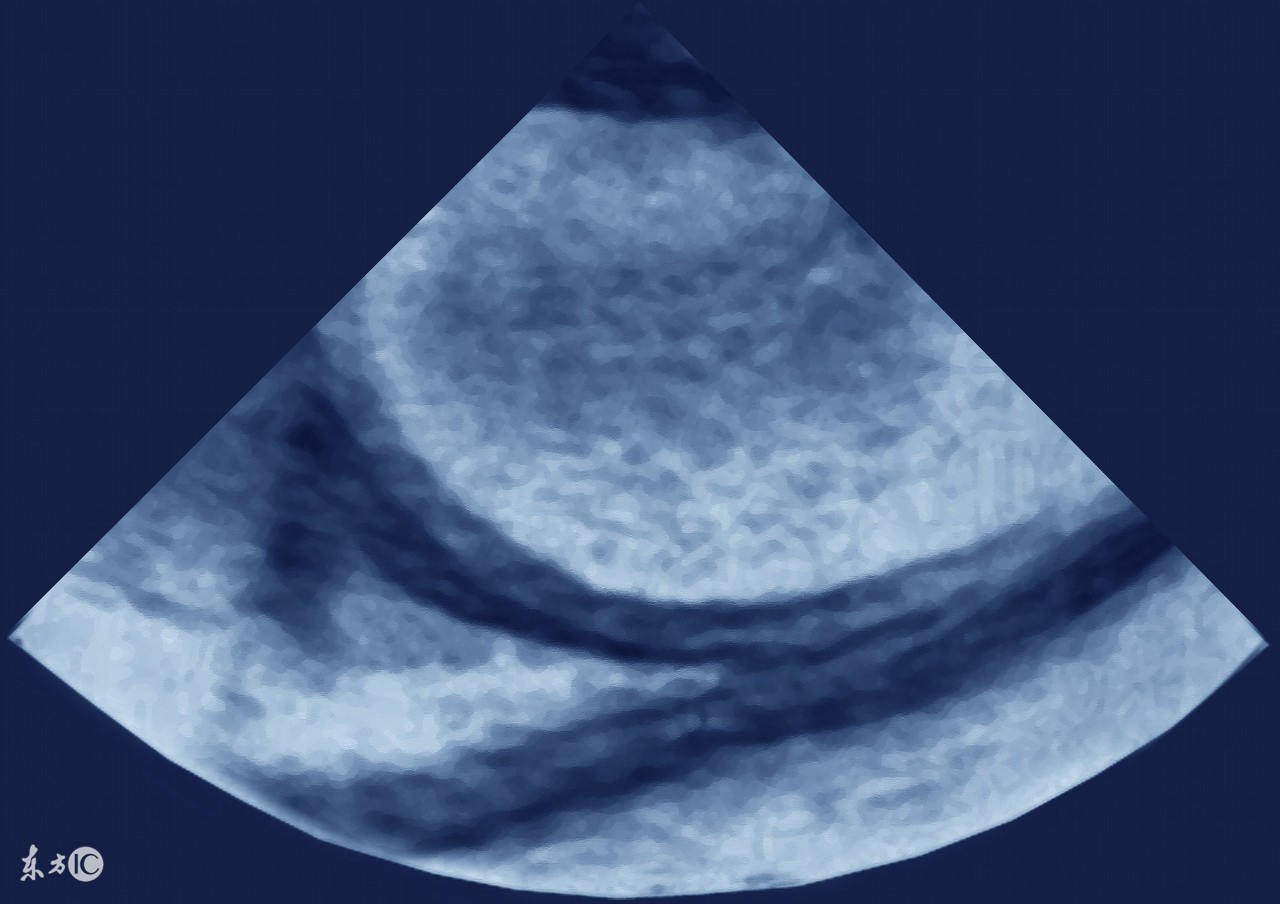

3、卵巢癌,包括输卵管癌、原发性腹膜癌,这三种癌症的治疗原则是一样的,这类癌症也是引起腹水的最常见原因之一,女性如果有大量的腹水,要首先排除卵巢癌可能,有针对性的重点查一查卵巢输卵管。